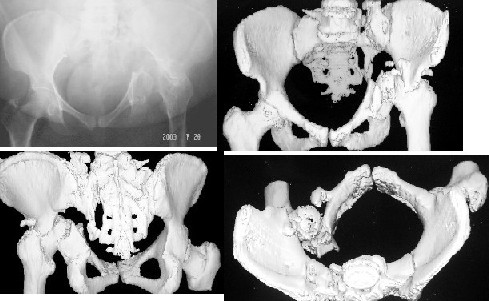

A 50 - years- old female patient had pelvic injury 18m ago due to MVA. Was treated by our neighbers, she had skeletal traction for 6 weeks.Her weight 88kg ,height 150cm, clinically walking dependantly on the frame with marked limping and 4cm shortening.hip flexion 80 degree, abduction 20 degree, painful movement of the hip.reviwing her serial x-rays, she had central dislocation with vertical shear involving the sacrum.No neurological deficiet.She had no medical diseases.Could we help this patient to improve her life?regards.

such a challenge , such type of pelvic fractures need to be tackled operatively with no hesitation, but it is too late now

for the time bieng you need to reconstruct the

acetabullum by bone grafts such a difficult surgery as the anatomy is distorted, following the creation of good floor and bone stock by bone grafts and stabilisation with reconstructive plates, you proceed as a second stage to total hip replacement

В подобных случаях первичное эндопротезирование крайне затруднено из-за нестабильности подвздошной кости. Даже при массивной костной пластике могут быть проблемы со сращением и формированием ложа для чашки протеза.

Мы применяем тактику двухэтапного лечения -реконструкция таза и вертлужной впадины, затем стандартное эндопротезирование.

Реконструкцию целесообразно выполнить с мобилизацией задних отделов крестца (обычно - чрескожная остеотомия под контролем ЭОПа), затем Y-образным чрезвертельным доступом обнажаем перелом, компрессия до контакта, можно использовать аппарат или тазовые щипцы с упором в надвертлужные области.

Фиксация реконструкционными пластинами.

Задние отделы фиксируются компрессирующими винтами.

Эндопротез через 3-5 месяцев, полезна предварительная КТ.